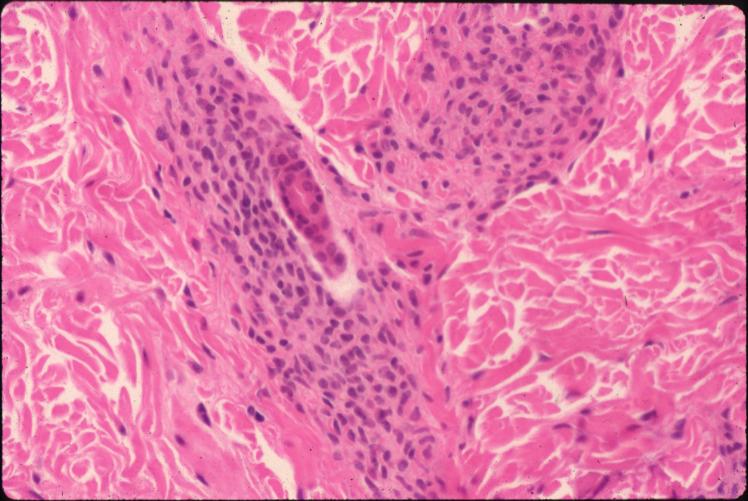

Congenital Nevus = الوحمة الخلقية